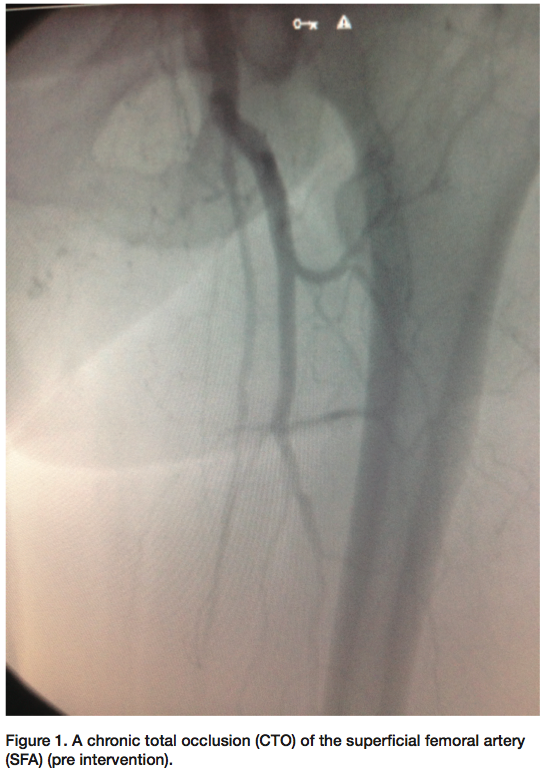

Some of the peripheral cases we perform include chronic total occlusions (CTOs) of the superficial femoral artery (SFA) (Figure 1-2). It may take some time crossing with a wire or crossing device on the proximal cap of the CTO. If trying to cross the CTO cannot be accomplished on the proximal cap of the SFA, gaining access distally may be a better option. Gaining access from a pedal or popliteal artery site is becoming more common. As we perform these interventions, we have access to the distal vessels to manipulate the guidewire up through the CTO from the distal cap first. Crossing the CTO with success from the distal cap works nicely most of the time. We have seen that the distal cap of the occlusion tends to be more crossable than the proximal cap. Once crossed and with verification that the wire is in the lumen of the vessel, the decision is made on what size sheath will be inserted. Depending on whether there are multiple lesions other than the CTO of the SFA, and whether your working access point is going to be from the distal access or from the femoral area, it might require a larger-size sheath. If you choose to work from the femoral area that is probably already accessed from the diagnostic films, then wiring through the lesion and into the sheath that is already across the bifurcation of the iliacs is a good method. Since your wire will be exchange length, grasping the wire tip is easily done. This way, you always have wire access during the entire procedure. The physician’s interventional plans determine the course of action that will be taken. If your interventional plans require you to use a smaller or larger wire (depending on what wire is used to make the initial crossing), the wire can always be exchanged out for a different size. Once the CTO is opened with a balloon, you can always change out the wire using a catheter such as the Seeker Crossing Support catheter (Bard PV) (or the physician’s preferred catheter). This is normally done if the physician decides to use an intravascular ultrasound (IVUS) catheter or any other device that requires the wire to be changed out (Volcano has both an .014 and .038 IVUS catheter).